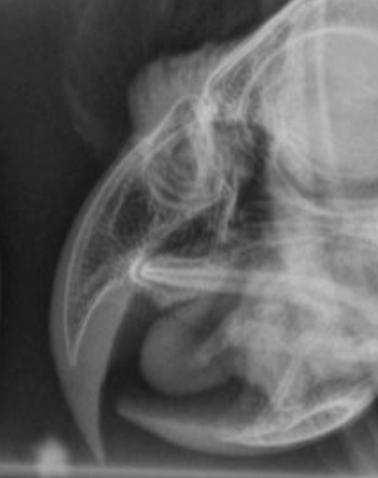

Guinea pig dentition

Guinea pigs have continuously growing teeth, just like rabbits, but the dental formula, shape and orientation of the teeth are quite different to rabbits. read more

Dental procedures in rabbits and guinea pigs

British Veterinary Zoological Society, in collaboration with the Rabbit Welfare Association & Fund, recently released a position statement on the use of anaesthesia in rabbit and guinea pig dental procedures. read more